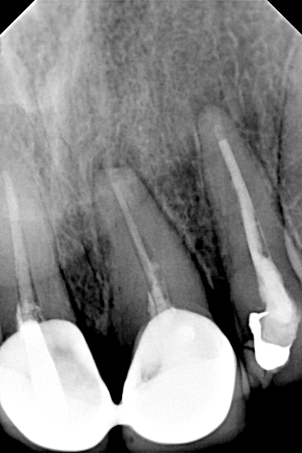

Ο ασθενής επιθυμούσε την προσθετική αποκατάσταση (με θήκη / στεφάνη δοντιού) του πρώτου γομφίου στην αριστερή πλευρά της κάτω γνάθου, καθώς το δόντι αυτό είχε ένα παλιό σφράγισμα το οποίο συνεχώς έσπαζε. Απαραίτητη προϋπόθεση για την έναρξη της διαδικασίας για τη στεφάνη δοντιού ήταν η κλινική και ακτινογραφική εξέταση του γομφίου. Μετά τη λήψη ακτινογραφίας αποκαλύφθηκε οτι το δόντι είχε μία παλιά απονεύρωση, η οποία ήταν ατελής εφόσον δεν εκτεινόταν σε όλο το μήκος των ριζικών σωλήνων του δοντιού ενώ φαινόταν ο τρίτος ριζικός σωλήνας στο δόντι να μην έχει εντοπιστεί. Μετά από συνεννόηση με τον ασθενή αποφασίστηκε η επανάληψη της απονεύρωσης του δοντιού, ώστε να εξασφαλιστεί ένα εγγυημένο προσθετικό αποτέλεσμα. Γενικότερα είναι επιθυμητό οι προσθετικές εργασίες να τοποθετούνται στα δόντια εφόσον έχουν γίνει όλες οι απαραίτητες εργασίες όπως απονεύρωση δοντιού, καθαρισμός των ούλων κ.α.

Μετά λοιπόν την αφαίρεση του παλιού σφραγίσματος εντοπίστηκε ο τρίτος ριζικός σωλήνας που δεν είχε βρεθεί στην παλιά πρώτη απονεύρωση, όπως δείχνει και η φωτογραφία της αρχικής κλινικής εικόνας. Στη συνέχεια καθαρίστηκαν και επεξεργάστηκαν όλοι οι ριζικοί σωλήνες (Για περισσότερες πληροφορίες Βλέπε Επανάληψη απονεύρωσης). Η διαδικασία ολοκληρώθηκε με την έμφραξη των ριζικών σωλήνων του δοντιού και την ανασύσταση της εκτεταμένης κοιλότητας με ειδικό άξονα υαλονημάτων και ρητίνη. Ακολούθως το δόντι τροχίστηκε, λήφθηκαν αποτυπώματα και όταν ο οδοντοτεχνίτης είχε έτοιμη τη θήκη του δοντιού αυτή κολλήθηκε στο δόντι.

ΠΡΙΝ